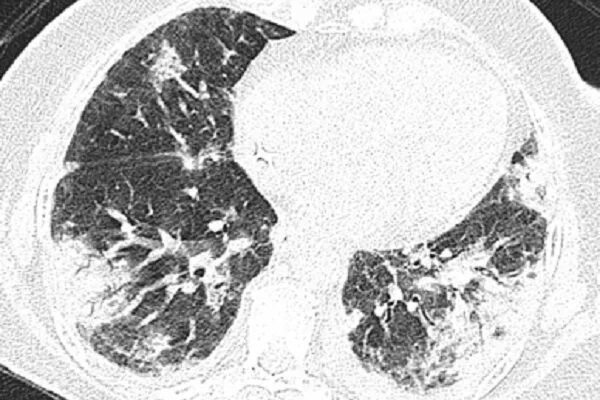

50 лет кт